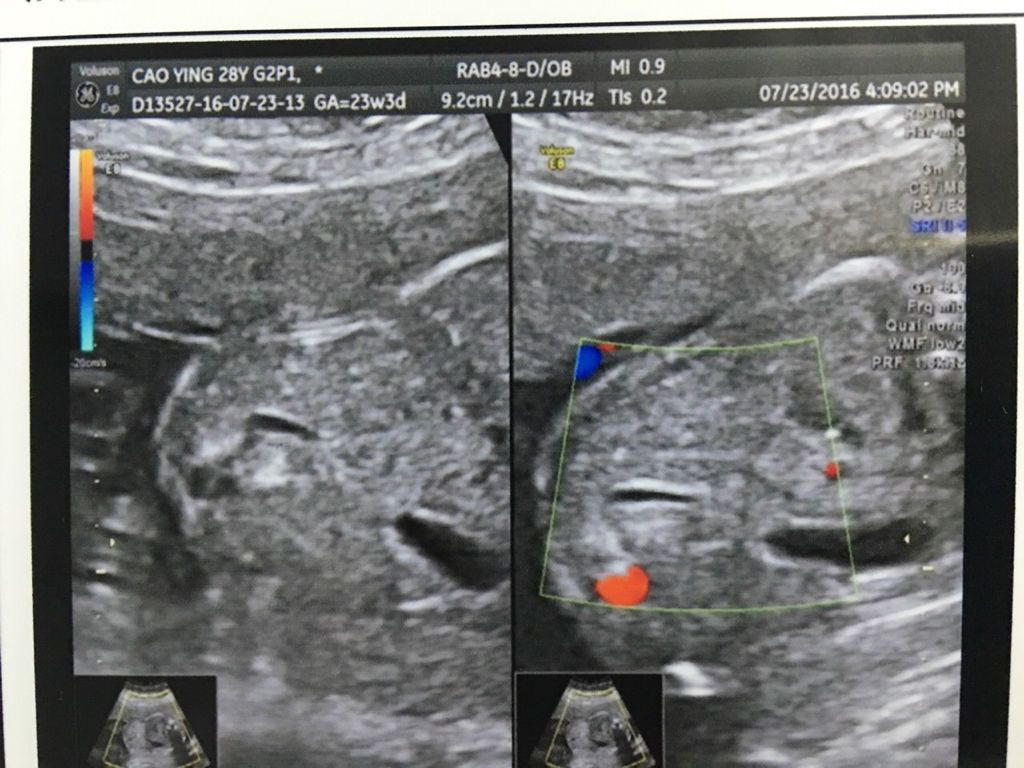

请专家帮我看看这是不是胎儿的胆囊,无比感激 请专家帮我看看这是不是胎儿的胆囊,无比感激.帮我看看是不是胎儿的胆囊,无比感激! 点击展开 匿名用户 2016-07-24 22:40 满意回答 你好,应该是的,胎儿期间也是可以看不到胆囊的。 hupozhouheng 2016-07-24 22:59 宝宝知道提示您:回答为网友贡献,仅供参考。 相关问题 我做完无痛人流后B超结果不是很好请专家帮我看看!万分感激! 哪位专家能帮我看看我儿子的黄疸问题,万分感激! 诚请专家帮我看看孕30周+2天的孕检报告,感激不尽~~~